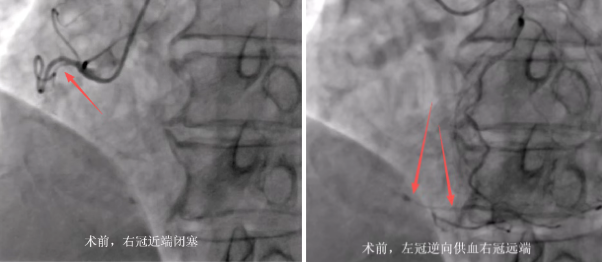

据了解,罗某,男,71岁,龙山里耶人,既往有鼻咽癌放化疗病史,近2年来反复有间断性胸痛、气促情况,多家医院救治,效果不佳,近期症状加重,于是慕名来到了县人民医院。经过心血管内科诊治,考虑有冠心病,建议行冠状动脉造影进一步评估,冠脉造影提示右冠慢性闭塞,前降支重度狭窄。

获得家属同意后,县人民医院心血管内科介入团队先尝试通过正向突破,更换多种CTO导丝均无法通过右冠闭塞病变到达远端血管真腔。而后考虑行逆向开通右冠CTO病变,在指引导管和微导管的双重支撑下,通过逆向导丝技术,在众多细如发丝的侧枝血管中反复探寻路径,多次更换具有不同性能的导丝。因为导丝和微导管的管径仅有0.3mm左右,在直径2mm的指引导管内将丝线穿进,这一操作的难度相当于裁缝拿着细线蒙着眼睛穿针眼,难度可想而知。经过反复调整方向,导丝最终顺利通过了闭塞病变。经过3小时后,终于成功完成逆向开通右冠CTO病变,于右冠远段至近端由远及近串联植入2枚支架,血管完全开通,手术成功。